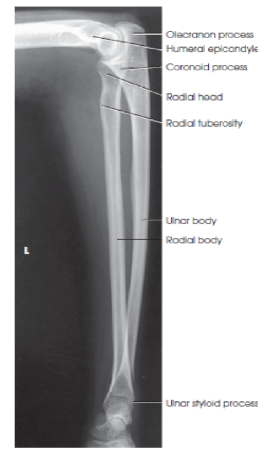

What structures are shown in a lateral forearm image?

entire forearm, including wrist and distal humerus in a true lateral position

eval - What structures should be superimposed in a lateral forearm image?

the radius and ulna at their distal end

the radial head over the coronoid process

humeral epicondyles

eval - what happens to the radial tuberosity in a lateral forearm position?

it faces anteriorly